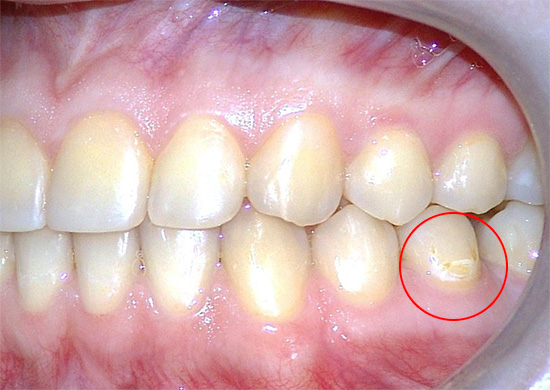

In alcuni casi, durante la gravidanza, la carie inizia solo il suo lavoro distruttivo (e molti cercano di aspettare questa volta), e le conseguenze più evidenti e sensibili del danno ai denti attendono una donna dopo il parto.

Tuttavia, il pericolo principale e più reale della carie durante la gravidanza è la possibilità del suo passaggio a una forma acuta, un grave danno a molti denti contemporaneamente e la loro perdita da parte di una donna in un tempo abbastanza breve. In altre parole, la carie è di solito più pericolosa per la madre che per il feto.

- Una diminuzione della concentrazione di calcio e composti del fluoro sia nella saliva che nel sangue a causa di un certo consumo per le esigenze di un embrione in via di sviluppo. Allo stesso tempo, il calcio non viene consumato dai denti stessi, come molti credono in modo errato. Ma la rimineralizzazione dello smalto e il suo rafforzamento, che si verificano sempre in altri periodi a causa dell'azione della saliva, durante la gravidanza possono rallentare o addirittura arrestarsi. Di conseguenza, lo smalto diventa debolmente mineralizzato e viene più facilmente danneggiato dai rifiuti acidi prodotti dai batteri.